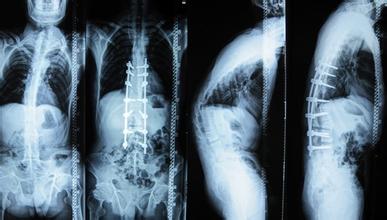

强制性脊柱炎疾病是令人非常厌恶的疾病,因为这样的疾病属于慢性疾病,疾病一旦发生不仅给患者带去健康危害病痛折磨,而且也是难以 的,所以对于这样的疾病一定要及早做好治疗在治疗的过程当中也应该注意好下面的事项。

在治疗强直性脊柱炎的过程当中,最值得注意的一点就是尽量避免使用激素,对于一些止痛药更是要警惕,千万不能滥用止痛药。由于强直性脊柱炎这种疾病在发 病的时候往往会伴随着关节疼痛的症状,严重的时候会让患者感觉到疼痛难忍痛不欲生,于是很多医生会给患者使用止痛药,这种做法虽然可以暂时性的缓解患者的 疼痛,但是值得一提的是大量的止痛药会麻醉人体神经,对后期的诊断治疗带来不利影响,并且长时间服用止痛药会导致患者产生药物依赖,对后期疾病的恢复十分 不利。

在治疗的过程当中一些医院为了尽快取得治疗效果往往会或多或少的对患者使用一些激素,这种做法确实会让患者在短时间内取得一定的治疗效果,但是往往会出现复发,并且强直性脊柱炎的每复发一次病情就会加重一次,所以在治疗的过程当中一定要警惕,尽量避免使用激素。